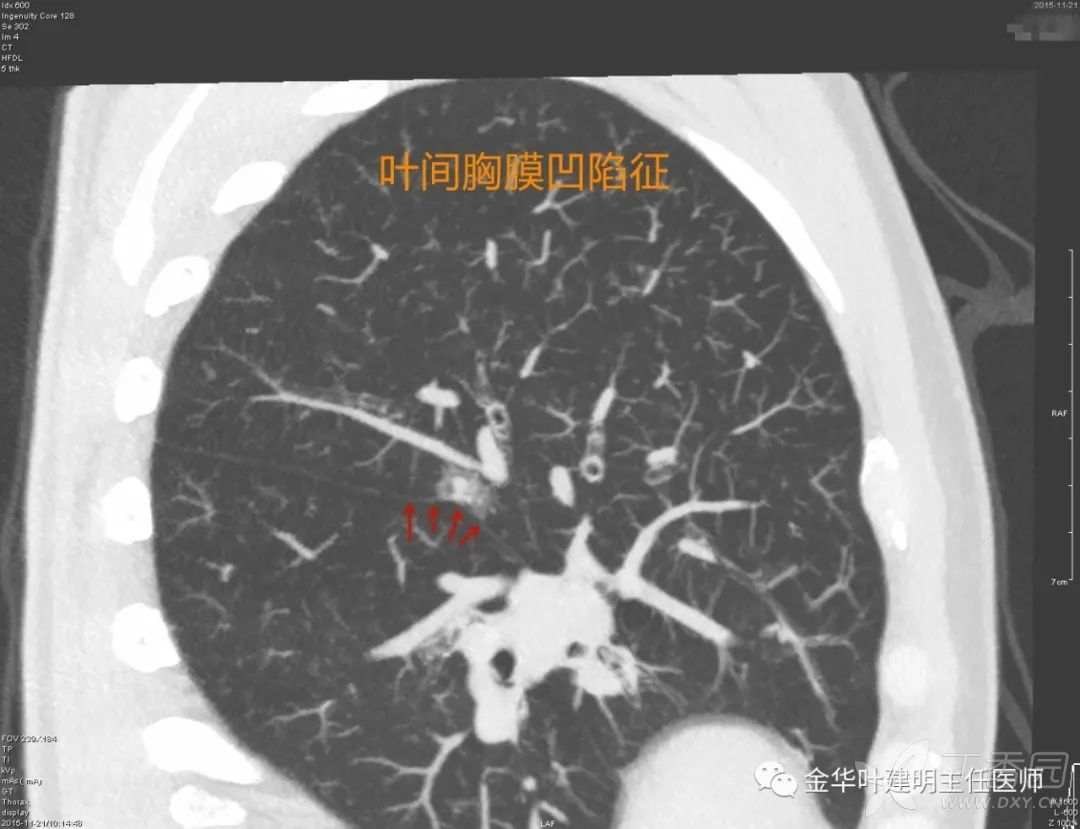

叶间胸膜凹陷征

叶间胸膜凹陷征:胸膜凹陷不单只是肋胸膜,之所以单独列开来讲,是因为提醒大家,叶间胸膜也是胸膜,邻近叶间裂部位的病灶,如果对叶间裂处有牵拉,也是胸膜凹陷征。